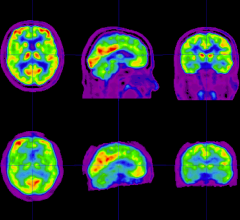

September 20, 2022 — Children and adolescents who have either recovered from COVID-19 or have long COVID show persistent ...